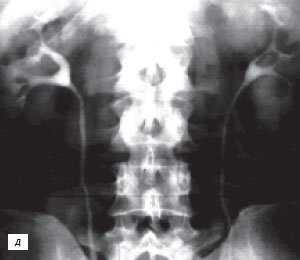

Наиболее частой причиной псевдоопухоли была "гипертрофия" столбов Бертена или "перемычки" паренхимы почек - у 153 (86,4%) пациентов (рис. 3 г-е). "Перемычки" паренхимы были отмечены не только при различных удвоениях чашечно-лоханочных систем почек, но и при различных их сращениях и незавершенных поворотах почек.

Рис. 3 (г-е). Псевдоопухоль гипертрофия Бертена (неполная "перемычка" паренхимы) в среднем отделе правой почки.

г) Эхограмма.

д) Экскреторная урограмма.

е) КТ с контрастным усилением.